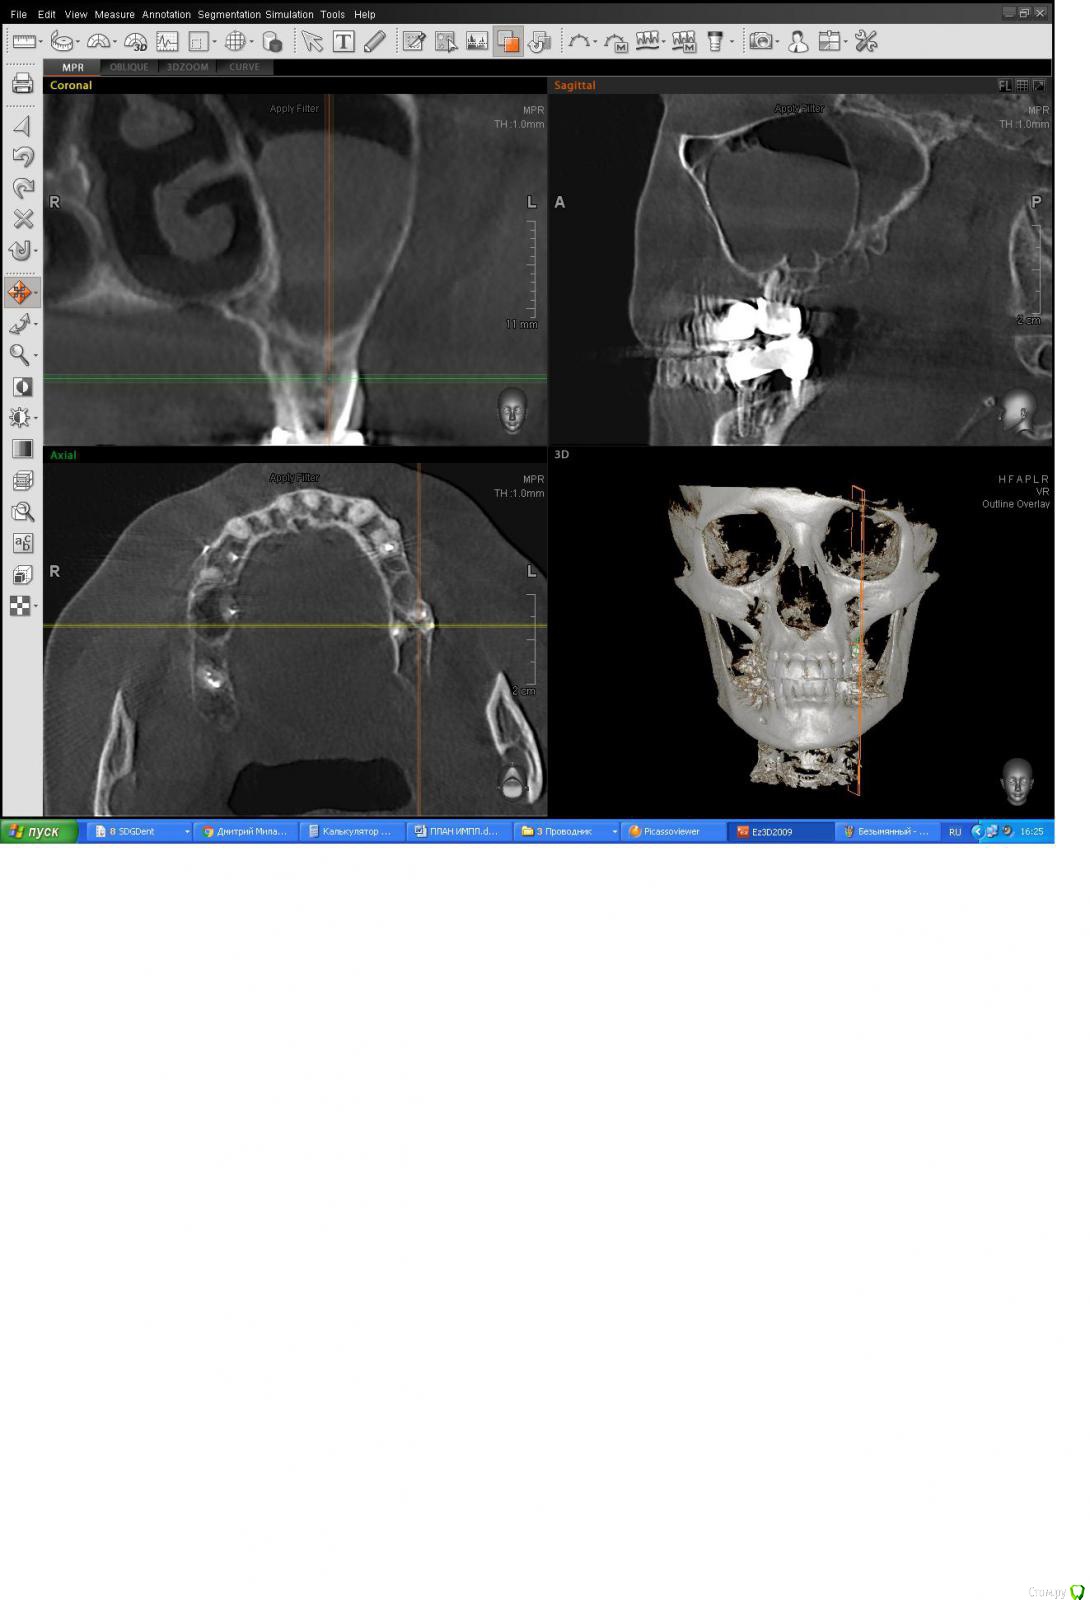

ПалСаныч Опубликовано 16 марта, 2017 Поделиться Опубликовано 16 марта, 2017 Присоединяюсь к мнению что синус делать нельзя. В пазухе полип. Пузырьки - это сопли. Убрать очаг хронической инфекции в виде зуба в певую очередь. Ссылка на комментарий

Dok22 Опубликовано 16 марта, 2017 Поделиться Опубликовано 16 марта, 2017 Шикарный одонтогенный гайморит от 26.Там и гранулема есть на медиальном корне и ей совсем не надо с пазухой сообщатся. 26 либо перелечивать либо удалять. Ссылка на комментарий

Irouil Опубликовано 16 марта, 2017 Поделиться Опубликовано 16 марта, 2017 Я не вижу в пазухе вообще ничего пока там такой отек. Зуб удалять/лечить/травить антибиотиками, пузырьки всегда в остром процессе есть - согласен с Пал Санычем, это сопли. Кт через два месяца. Ссылка на комментарий